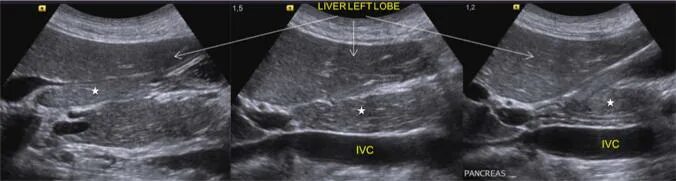

Поджелудочная диффузно неоднородная